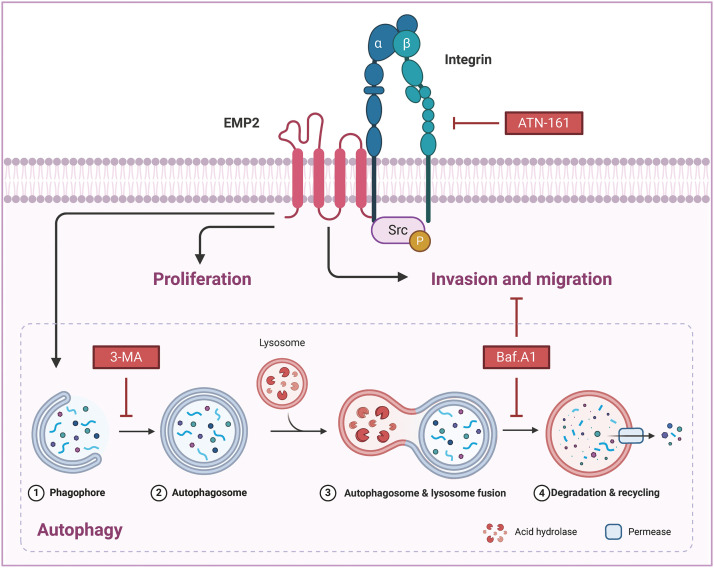

Bioinformatic and immunohistochemical analysis of tissue microarrays have confirmed the significant upregulation of EMP2 in HCC tissues. In vitro and in vivo studies have shown that downregulation of EMP2 results in a moderate reduction in the proliferation and invasive capacity of HCC cells. Conversely, overexpression of EMP2 enhances the invasive capacity of HCC cells and induces autophagy. Initial investigations into the molecular mechanisms underlying EMP2-mediated enhancement of HCC cell invasion have revealed the dual regulation of EMP2-induced autophagy and the integrin pathway, which synergistically influence the invasive and metastatic potential of HCC cells.

EMP2 activated autophagy via integrin signaling pathway

To further elucidate the correlation between EMP2, autophagy, and integrins in HCC, ATN-161, bafilomycin A1 (Baf.A1), and 3-methyladenine (3-MA) were added to HepG2 cells overexpressing EMP2, and the changes in cellular invasion capacities and their effects on related proteins were observed. ATN-161, an integrin inhibitor, has demonstrated anti-tumor efficacy in advanced solid tumors [ref. 38]. Baf.A1 and 3-MA are potent inhibitors of autophagy [ref. 39,ref. 40]. As illustrated in Fig. 7A, both ATN-161 and Baf.A1 significantly inhibit the invasive capacity of HepG2 cells in the extracellular matrix. Furthermore, EMP2 overexpression substantially enhances the invasive ability of HepG2 cells, resulting in a significant increase in the number of transmembrane cells. However, the addition of ATN-161 and Baf.A1 significantly suppresses the promoting effect of EMP2 on the invasive ability of HepG2 cells. These findings indicate that the invasive process regulated by EMP2 is influenced by both integrin and autophagy. Integrins and EMP2 are transmembrane proteins situated on the cell surface [ref. 10]. Previous studies have demonstrated a direct interaction between integrins and EMP2, with both being involved in various physiological and biochemical processes, such as cell proliferation and signaling [ref. 10,ref. 14]. When engaged in regulating cellular processes, integrins can activate multiple signaling molecules, such as Src, recruit kinase complexes, phosphorylate downstream signaling molecules, activate cell signaling pathways, and regulate tumor cell growth and metabolism, thereby influencing tumor development [ref. 41,ref. 42]. Fig. 7B illustrates that in the empty vector control group, the expression of EMP2 and p-Src is significantly inhibited by ATN-161. In contrast, the addition of ATN-161 suppresses the increased expression of EMP2 and p-Src caused by EMP2 overexpression in the EMP2 overexpression group. Moreover, the evident co-localization of EMP2 and p-Src suggests a direct interaction. These findings indicate that the expression of EMP2 and p-Src, as well as their interaction, are partially regulated by autophagy. As shown in Fig. 7C, the expression of EMP2 and p-Src was significantly inhibited by Baf.A1 in the empty vector control group. However, the addition of Baf.A1 suppresses the increased expression of EMP2 and p-Src caused by EMP2 overexpression in the EMP2 overexpression group (Fig. 7C). Furthermore, EMP2 and p-Src exhibit a certain degree of co-localization, suggesting a possible direct interaction between the two. These results suggest that the expression of EMP2 and p-Src, as well as their interaction, are partially regulated by autophagy. Fig. 7D illustrates that GFP-LC3 was transiently transfected into HepG2 cells of different groups, and the lysosome probe Lysotracker was added to observe the effects of 3-MA and different EMP2 expression states on the interaction between autophagosomes and lysosomes. The results indicate that in the EMP2 overexpression group of HepG2 cells, the number of autophagosomes and the fusion of autophagosomes with lysosomes significantly increased. The enhanced autophagy in HepG2 cells caused by EMP2 overexpression can be partially reversed by 3-MA.

Our analysis of transcriptome data from 374 liver cancer patients from the TCGA database revealed that only EMP2 shows significant differences in expression between liver cancer and normal liver tissues, suggesting its significant role in the onset of liver cancer. EMP2’s expression exhibits organ-specific traits, and numerous studies have reported its varied expression across different tumors. Tissue microarrays indicate that EMP2 levels are significantly lower in low-grade gliomas than in high-grade gliomas; however, in GBM patients, EMP2 expression does not significantly impact survival times. In breast malignant phyllodes tumors, EMP2 is downregulated in epithelial cells but upregulated in stromal components. Moreover, detailed analysis of EMP2 in potential precancerous lesions suggests that EMP2 positivity strongly predicts the progression of endometrial cancer. In nasopharyngeal carcinoma, EMP2 expression is generally weak or absent in tumor tissues but moderate to strong in adjacent non-tumor tissues, with higher levels of EMP2 associated with significantly longer survival times. Our comprehensive analysis of pan-cancer transcriptomic data from databases such as TIMER and Oncomine shows that EMP2 expression varies significantly across different cancers. In BRCA, THCA, ESCA, and LIHC, EMP2 mRNA is significantly elevated compared to normal tissues; meanwhile, in KICH, LUAD, KIRP, PRAD, LUSC, and HNSC, EMP2 mRNA levels are markedly lower than in corresponding normal tissues, confirming previous reports and underscoring the complexity of EMP2’s role in cancer biology. We conducted immunohistochemical analyses to explore the expression patterns of EMP2 protein across various stages of liver disease, ranging from normal liver tissue to hepatocellular carcinoma, using a comprehensive liver disease tissue microarray. Through a comparative analysis of gene expression data from hepatocellular carcinoma samples with high vs. low EMP2 expression, we identified 28 genes associated with autophagy, such as IGFBP2 and BNIP3, suggesting a potential linkage between EMP2 and autophagy in liver cancer. Silencing EMP2 markedly reduced the proliferation of HepG2 and Huh-7 cells, particularly in Huh-7, yet did not significantly increase apoptosis in HepG2 cells. EMP2, a protein that spans the cell membrane four times, is crucial for binding various cell surface molecules and facilitates transmembrane transport of materials, influencing cell adhesion and migration—key processes in the metastatic cascade of tumor cells. Therefore, we hypothesize that EMP2 could play a significant role in the invasion and metastasis of liver cancer cells. Further validation came from Transwell assays, which showed that EMP2 knockdown significantly impaired the invasive capabilities of HepG2 and Huh-7 cells through the basement membrane, although scratch tests (Data not shown) indicated no substantial impact on their migration abilities. In liver cancer cells stably transduced with shEMP2 lentivirus, transient transfection with the GFP-LC3 plasmid resulted in a noticeable reduction in the green punctate fluorescence of LC3 in the cytoplasm of the interference group compared to the control group, indicating reduced autophagy. This observation was supported by transmission electron microscopy, which revealed a significant decrease in autophagosomes in the EMP2-silenced cells. Quantitative PCR and Western blot analyses further demonstrated that reducing EMP2 in HepG2 and Huh-7 cells decreased the levels of autophagy-related proteins BNIP3 and LC3 and increased the expression of the protein SQSTM1. Additionally, a significant decrease in the expression of integrin ITGA5 was observed, correlating with the reduced invasive capabilities. These findings collectively confirm that downregulating EMP2 significantly inhibits autophagy in liver cancer cells, impacting their invasive and metastatic potential (Fig. 9).

Integrins, heterodimeric receptors composed of α and β subunits that form non-covalent bonds on the cell surface, mediate interactions between cells and between cells and the extracellular matrix (ECM). They play a crucial role in regulating various cellular physiological processes, including invasion, migration, proliferation, and differentiation. EMP2 and integrins, both being transmembrane proteins, have been reported to interact directly or indirectly through the recruitment of the kinase complex FAK/Src, leading to the phosphorylation of downstream proteins and activation of corresponding signaling pathways, thus regulating the invasive and metastatic behaviors of tumor cells. Our study also found that EMP2 downregulation led to a significant reduction in ITGA5 protein expression, weakening the invasion ability of liver cancer cells and resulting in fewer and smaller experimental lung metastases; conversely, overexpression had the opposite effect. Knocking down EMP2 expression in HepG2 and Huh-7 cells significantly reduced autophagosomes, and the overexpressed EMP2 partially reversed the down-regulated Integrin a5 caused by ATN-161 (Fig. 7B). We also discovered that overexpressing EMP2 could induce autophagy in HepG2 cells, with a significant increase in the autophagy marker proteins LC3-I and LC3-II. Following the addition of the integrin inhibitor ATN-161, EMP2 expression was partially reversed, LC3-II expression significantly downregulated, and SQSTM1 expression significantly upregulated, indicating that the expression of EMP2 and p-Src and their interaction are partially regulated by autophagy. The use of both the integrin inhibitor ATN-161 and the autophagy inhibitor Baf.A1 significantly inhibited the increased invasion ability of HepG2 cells caused by overexpression of EMP2, further validating that the EMP2-promoted invasion process is doubly regulated by integrins and autophagy, highlighting the complex interplay between these molecular mechanisms in liver cancer progression. However, several limitations persist in the current research. Firstly, the study utilized only two HCC cell lines for in vitro experiments; incorporating additional cell lines would enhance the generalizability of the findings. Moreover, the interactions between EMP2 and autophagy/integrin pathways require further characterization through multi-omics approaches. The mechanistic insights are predominantly based on correlation; direct and causal evidence is lacking in certain areas. The role of EMP2 in HCC stem cells, drug resistance, and the tumor microenvironment remains uninvestigated. In summary, although novel insights were provided, further robust validation studies are necessary to address these limitations before EMP2 can be developed as a clinical target in HCC.

Bioinformatics and immunohistochemical analysis consistently demonstrate that EMP2 expression increases as the disease progresses from hepatitis to cirrhosis and ultimately to HCC. Both in vitro and in vivo studies have proven that reducing EMP2 expression not only inhibits autophagy but also diminishes the proliferation and invasive capabilities of HCC cells. Initial molecular studies indicate that EMP2 enhances the invasiveness and metastatic tendencies of HCC cells by activating integrins and implementing a bidirectional regulatory mechanism, processes that are intricately linked to the autophagy triggered by EMP2. Thus, EMP2 is recognized not only as an effective marker for diagnosing HCC metastasis but also as a potential target for future biotherapeutic interventions against HCC.